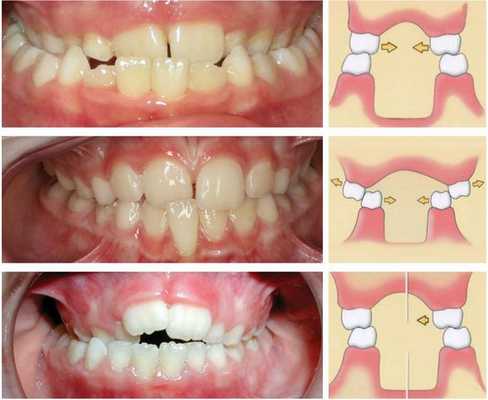

- глубокий прикус - глубокое (более чем на 50%) перекрытие верхними резцами нижних

- перекрестный прикус - нарушение нормального соотношения зубных дуг, их смещение вбок относительно друг друга

В зависимости от расположения зубов при при смыкании челюстей выделяют три типа перекрёстного прикуса:

- Буккальный — когда верхний зубной ряд сужен, а нижний ряд расширен с одной или двух сторон. При смыкании челюстей щёчные бугры нижних зубов перекрывают верхние. Этот тип может быть как со смещением нижней челюсти, так и без него.

- Лингвальный — когда верхний зубной ряд расширен, а нижний сужен также с одной или обеих сторон. При смыкании челюстей нёбные бугры верхних зубов перекрывают щёчные бугры нижних.